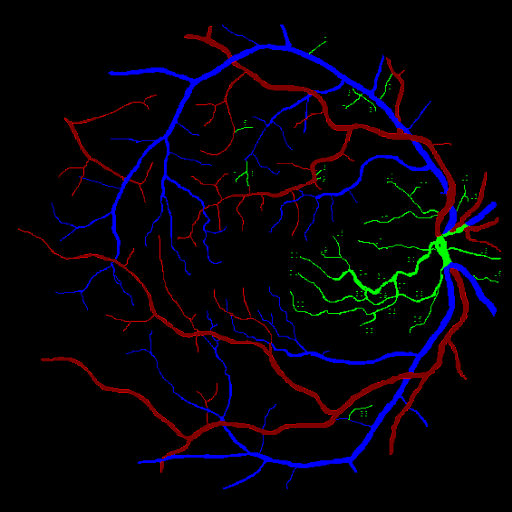

For better explainability of the result, Tables 4 and 5 and the activation map of the final layer can be observed. In Fig. 7, the first image corresponds to the ground image, the first column corresponds to the activation map of the artery and vein channel of the Attention-UNet Model trained for Separate Artery-Vein segmentation, and the second column corresponds to the activation map of artery and vein channel of the Attention-WNet Model trained for binary segmentation model. It can be observed that the latter model is more confident about the vessel’s nature than the former. The fundus image, ground truth, and the corresponding sample outputs provided by Attention UNet and Attention-WNET are shown in Figure 6. It can be observed that some of the vein pixels have been marked as artery pixels by Attention UNet. In this case, Attention WNet predicts better than Attention UNet. It shows the proposed approach’s capability to distinguish between arteries and veins. It is also observed that the model is comparatively more confident about artery pixels than veins, further confirming the complexity involved in identifying veins even though the latter performs comparatively better.

Refer to caption

(a)

(b)

(c)

(d)

Figure 6: Comparing Attention UNet and Attention WNet output for a given fundus image